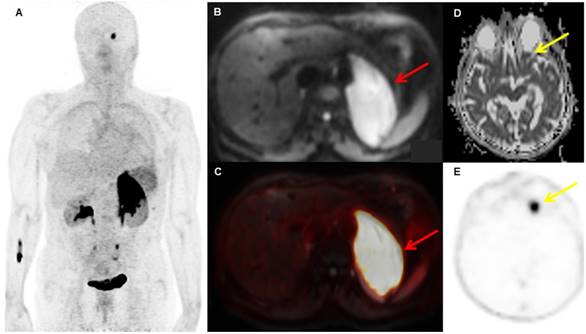

Figure 1

A patient with biopsy-proven MALT lymphoma of the left adrenal gland. The adrenal MALT lymphoma shows high [68Ga]Ga-Pentixafor uptake (A, SUVmax 25.4), and is also well-visualized on the DWI b800 image (B, red arrow, C, fused PET/MRI). In addition, an area of increased uptake on PET is visible in the left orbit (E, yellow arrow), which was initially missed on MRI, but, in retrospect, showed restricted diffusion on the ADC map upon consensus reading (D, yellow arrow); this orbital lesion also proved to be MALT lymphoma at histology.